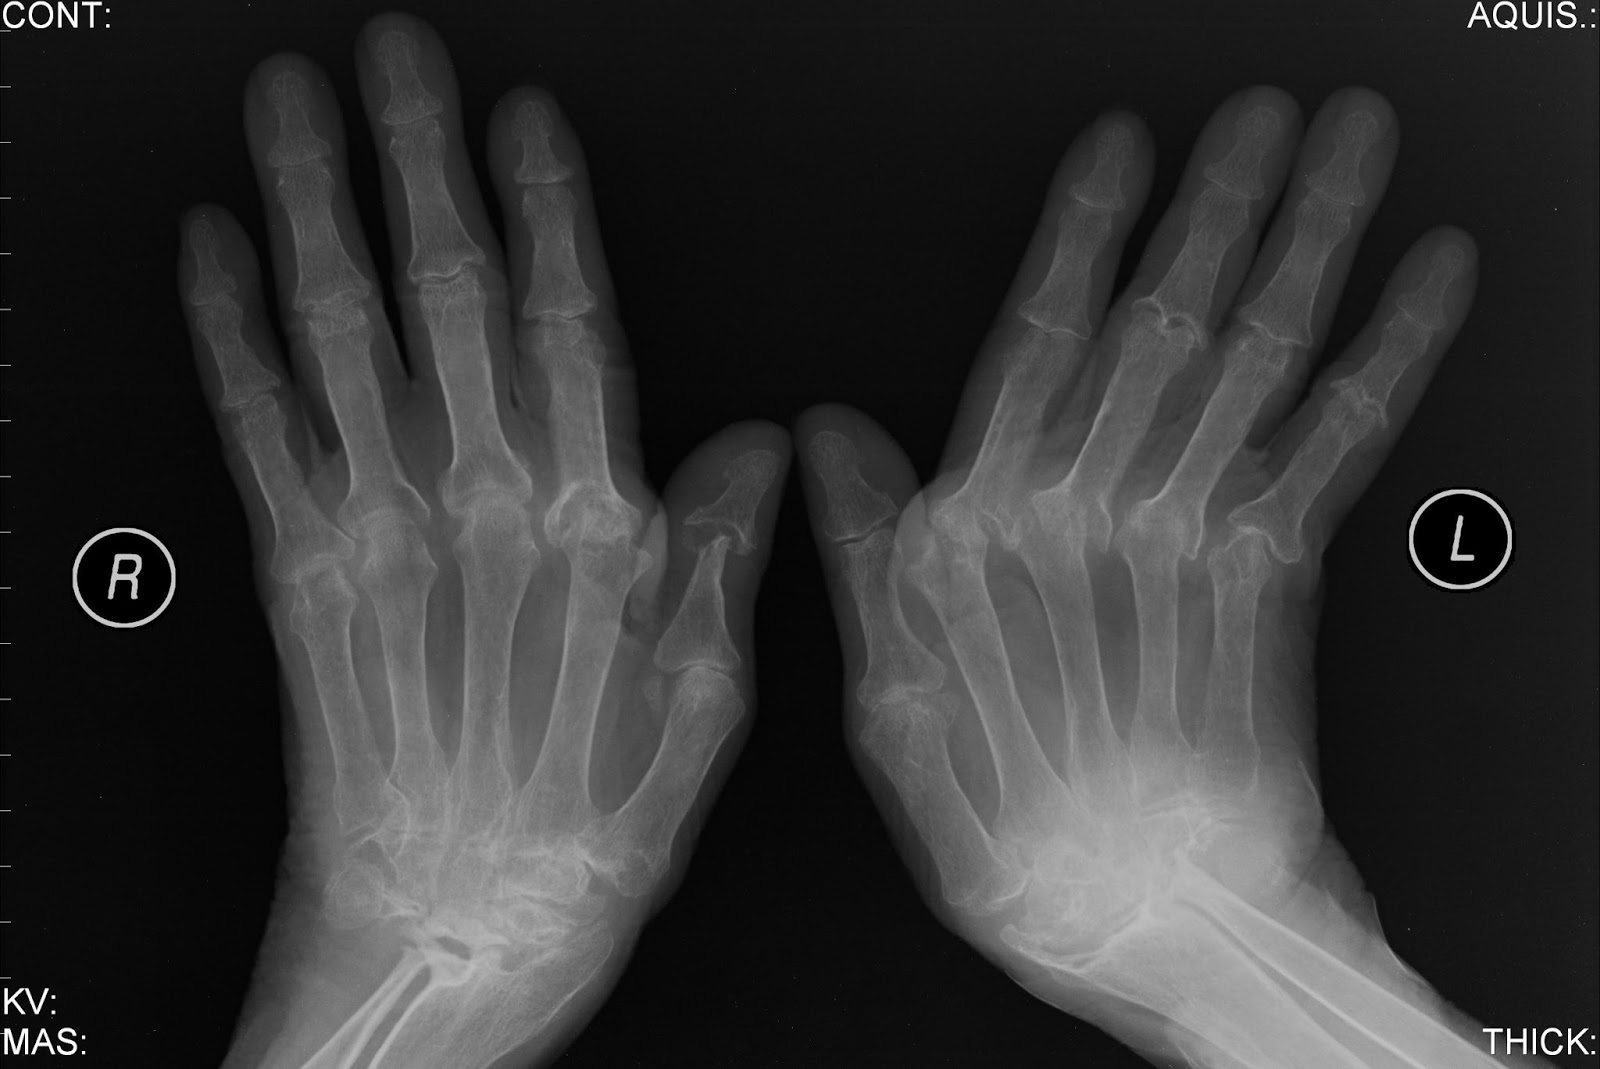

– Hoje pegam facilmente. Tenho artrite ( ABAIXO ) , artrose, bico de papagaio...